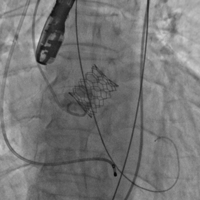

上午11时许,手术直播开始。手术经股动脉入路,使用23#预扩球囊进行跨瓣预扩,预扩后患者突发室颤,血压下降,考虑与患者心功能较差,预扩后反流增加有关。手术团队具有丰富经验,临危不乱,立即予患者电复律、心肺复苏,同时迅速为患者植入一枚25#Renatus介入主动脉瓣,以保证患者左心室-主动脉单向血流。瓣膜植入后,予以补液、血管活性药物治疗,患者血流动力学逐渐稳定,生命体征恢复平稳,术后超声及造影示:瓣膜位置理想,无瓣中返流及瓣周漏,TEE提示主动脉瓣平均跨瓣压差由术前38mmHg降至5mmHg,峰值流速由术前4.3m/s降至1.8m/s。整个手术在一小时内结束,最终获得成功。

球囊预扩 瓣膜释放